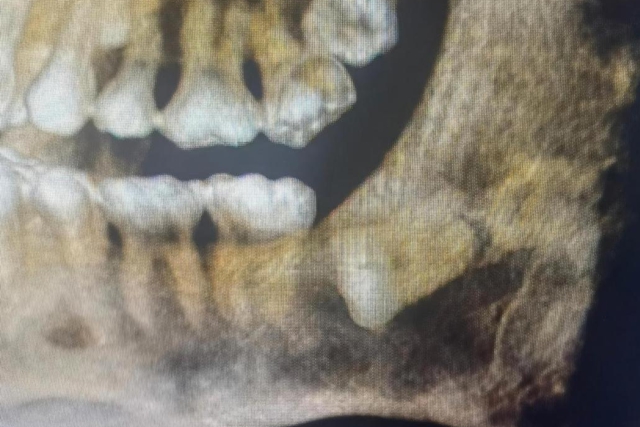

随后小伙做了口腔颌面锥形束 CT(口腔CBCT)检查,真相才水落石出:这是一颗水平低位阻生智齿,整颗牙横着埋在牙龈里,完全没法正常长出来。

不仅如此,牙冠周围的组织还一直分泌液体,慢慢形成了包裹着牙冠的含牙囊肿,囊肿已经波及旁边牙齿的牙根,还挨着下颌神经管,要是贸然拔牙,很容易伤到邻牙和神经管。

好在陈高翔医生做了周密的手术规划,术中又采用微创操作,顺利帮小伙拔掉了这颗 “隐藏的心头大患”,还精准避开了相邻牙齿和下颌神经管。术后一段时间,小伙的伤口恢复得特别好,既没有出现邻牙发炎疼痛的情况,也没有任何神经损伤的不适症状。